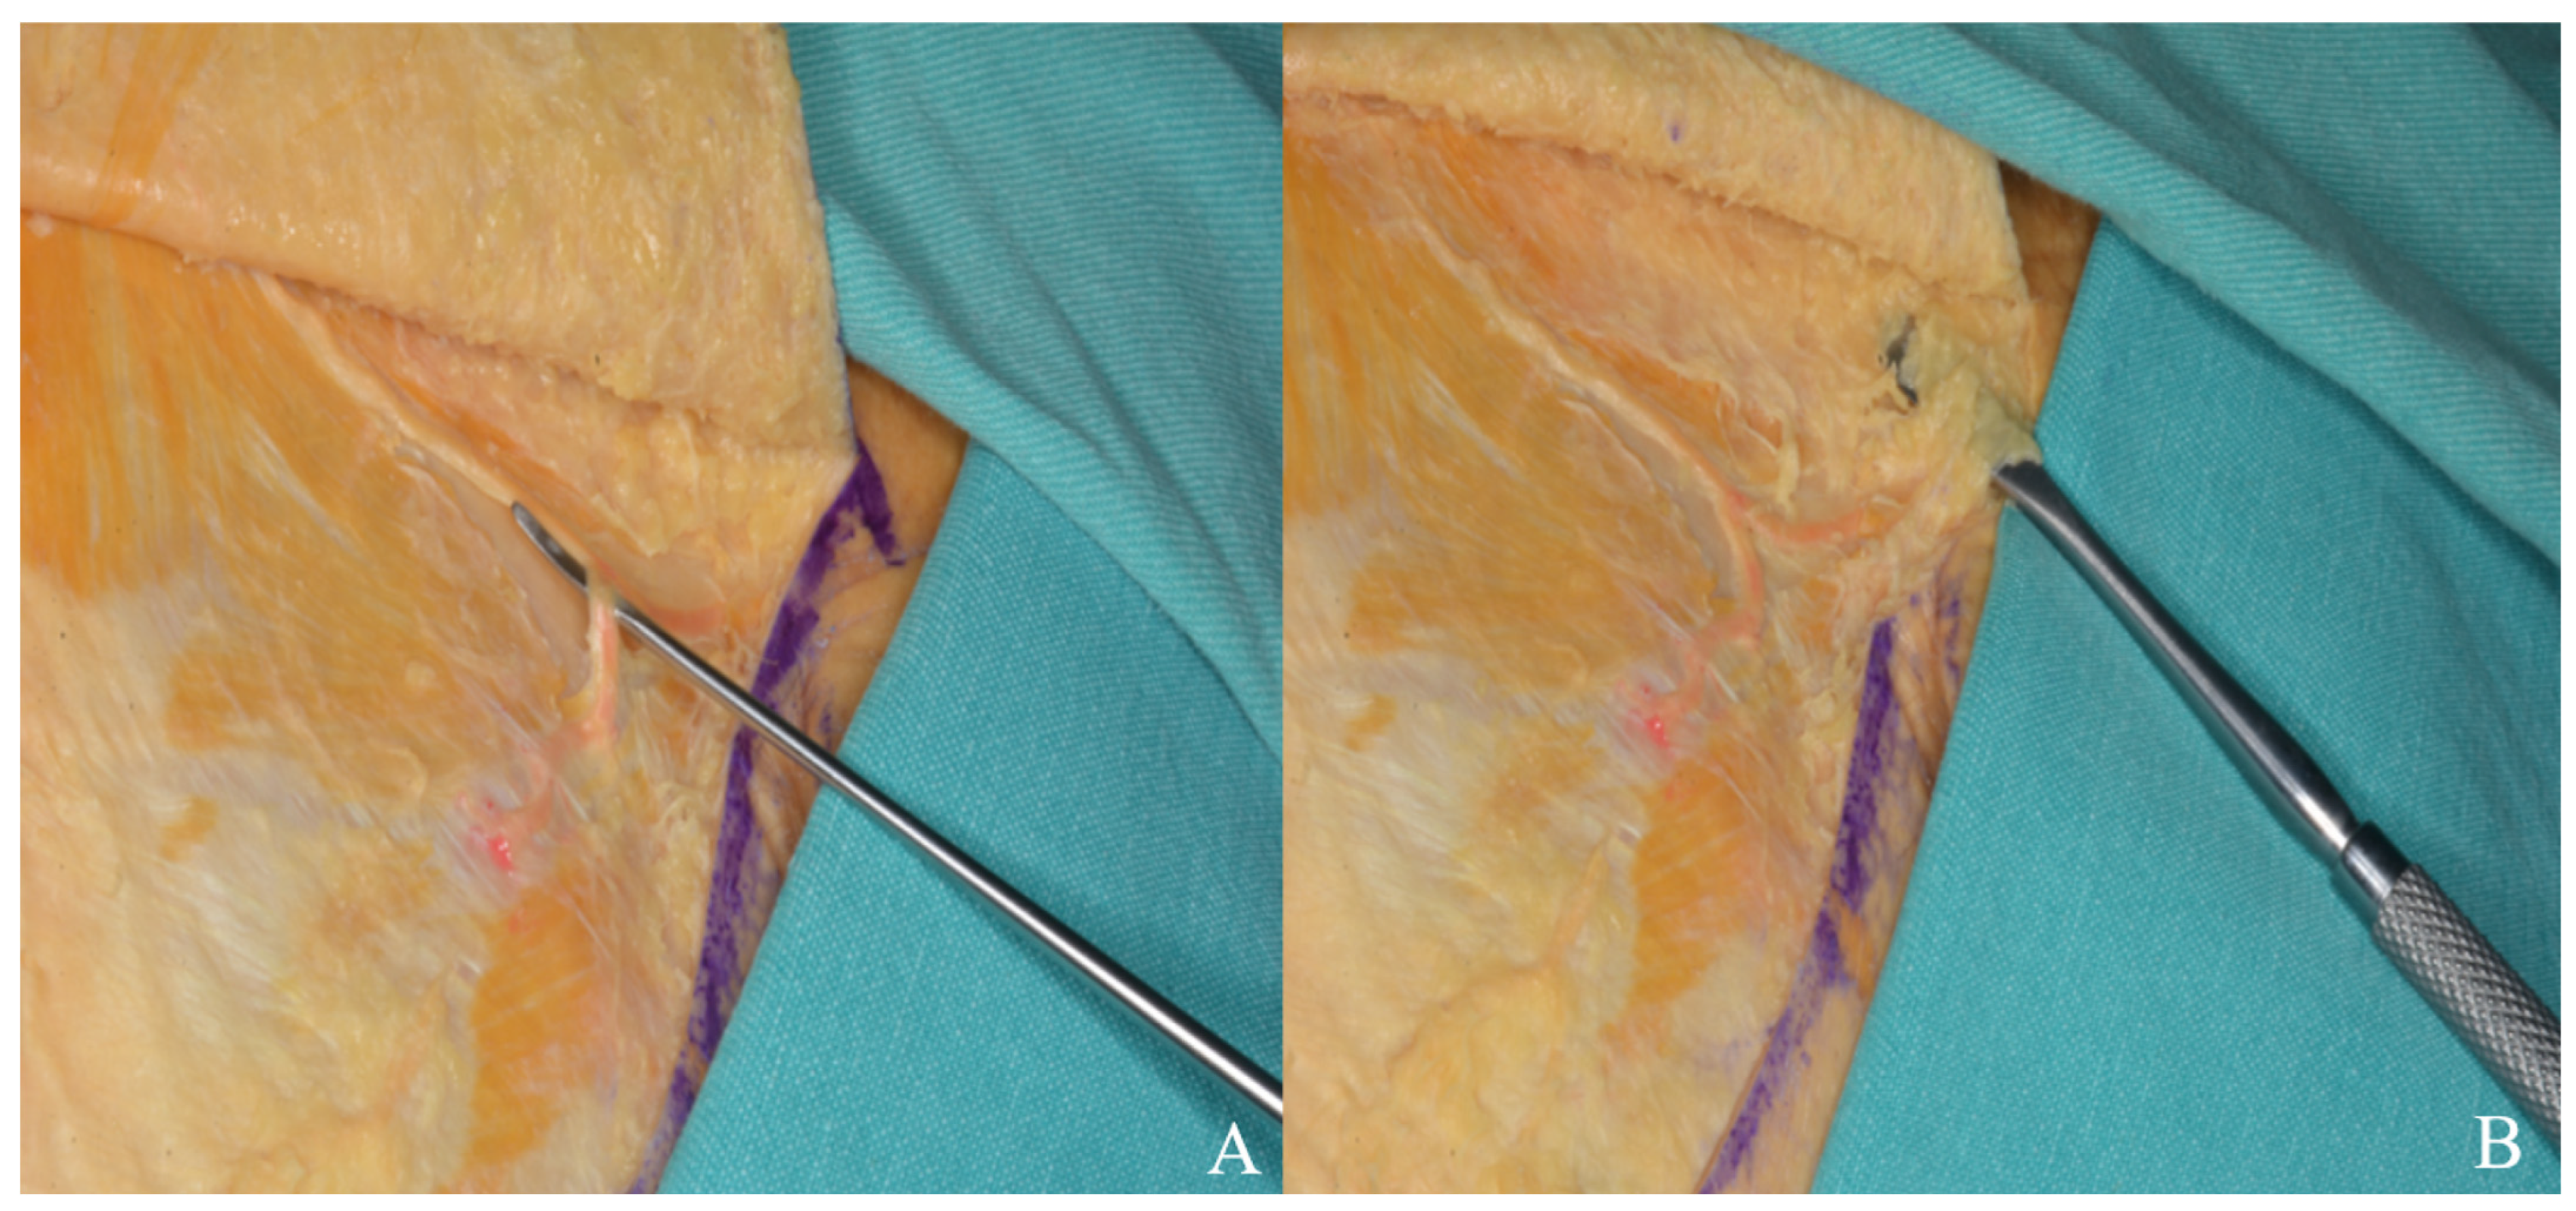

3.1.1. Incision

3.1.2. Interfacial, Subfascial Dissection Technique and Temporal Muscle Elevation

3.2.1. Incision

3.2.2. Temporal Muscle Elevation